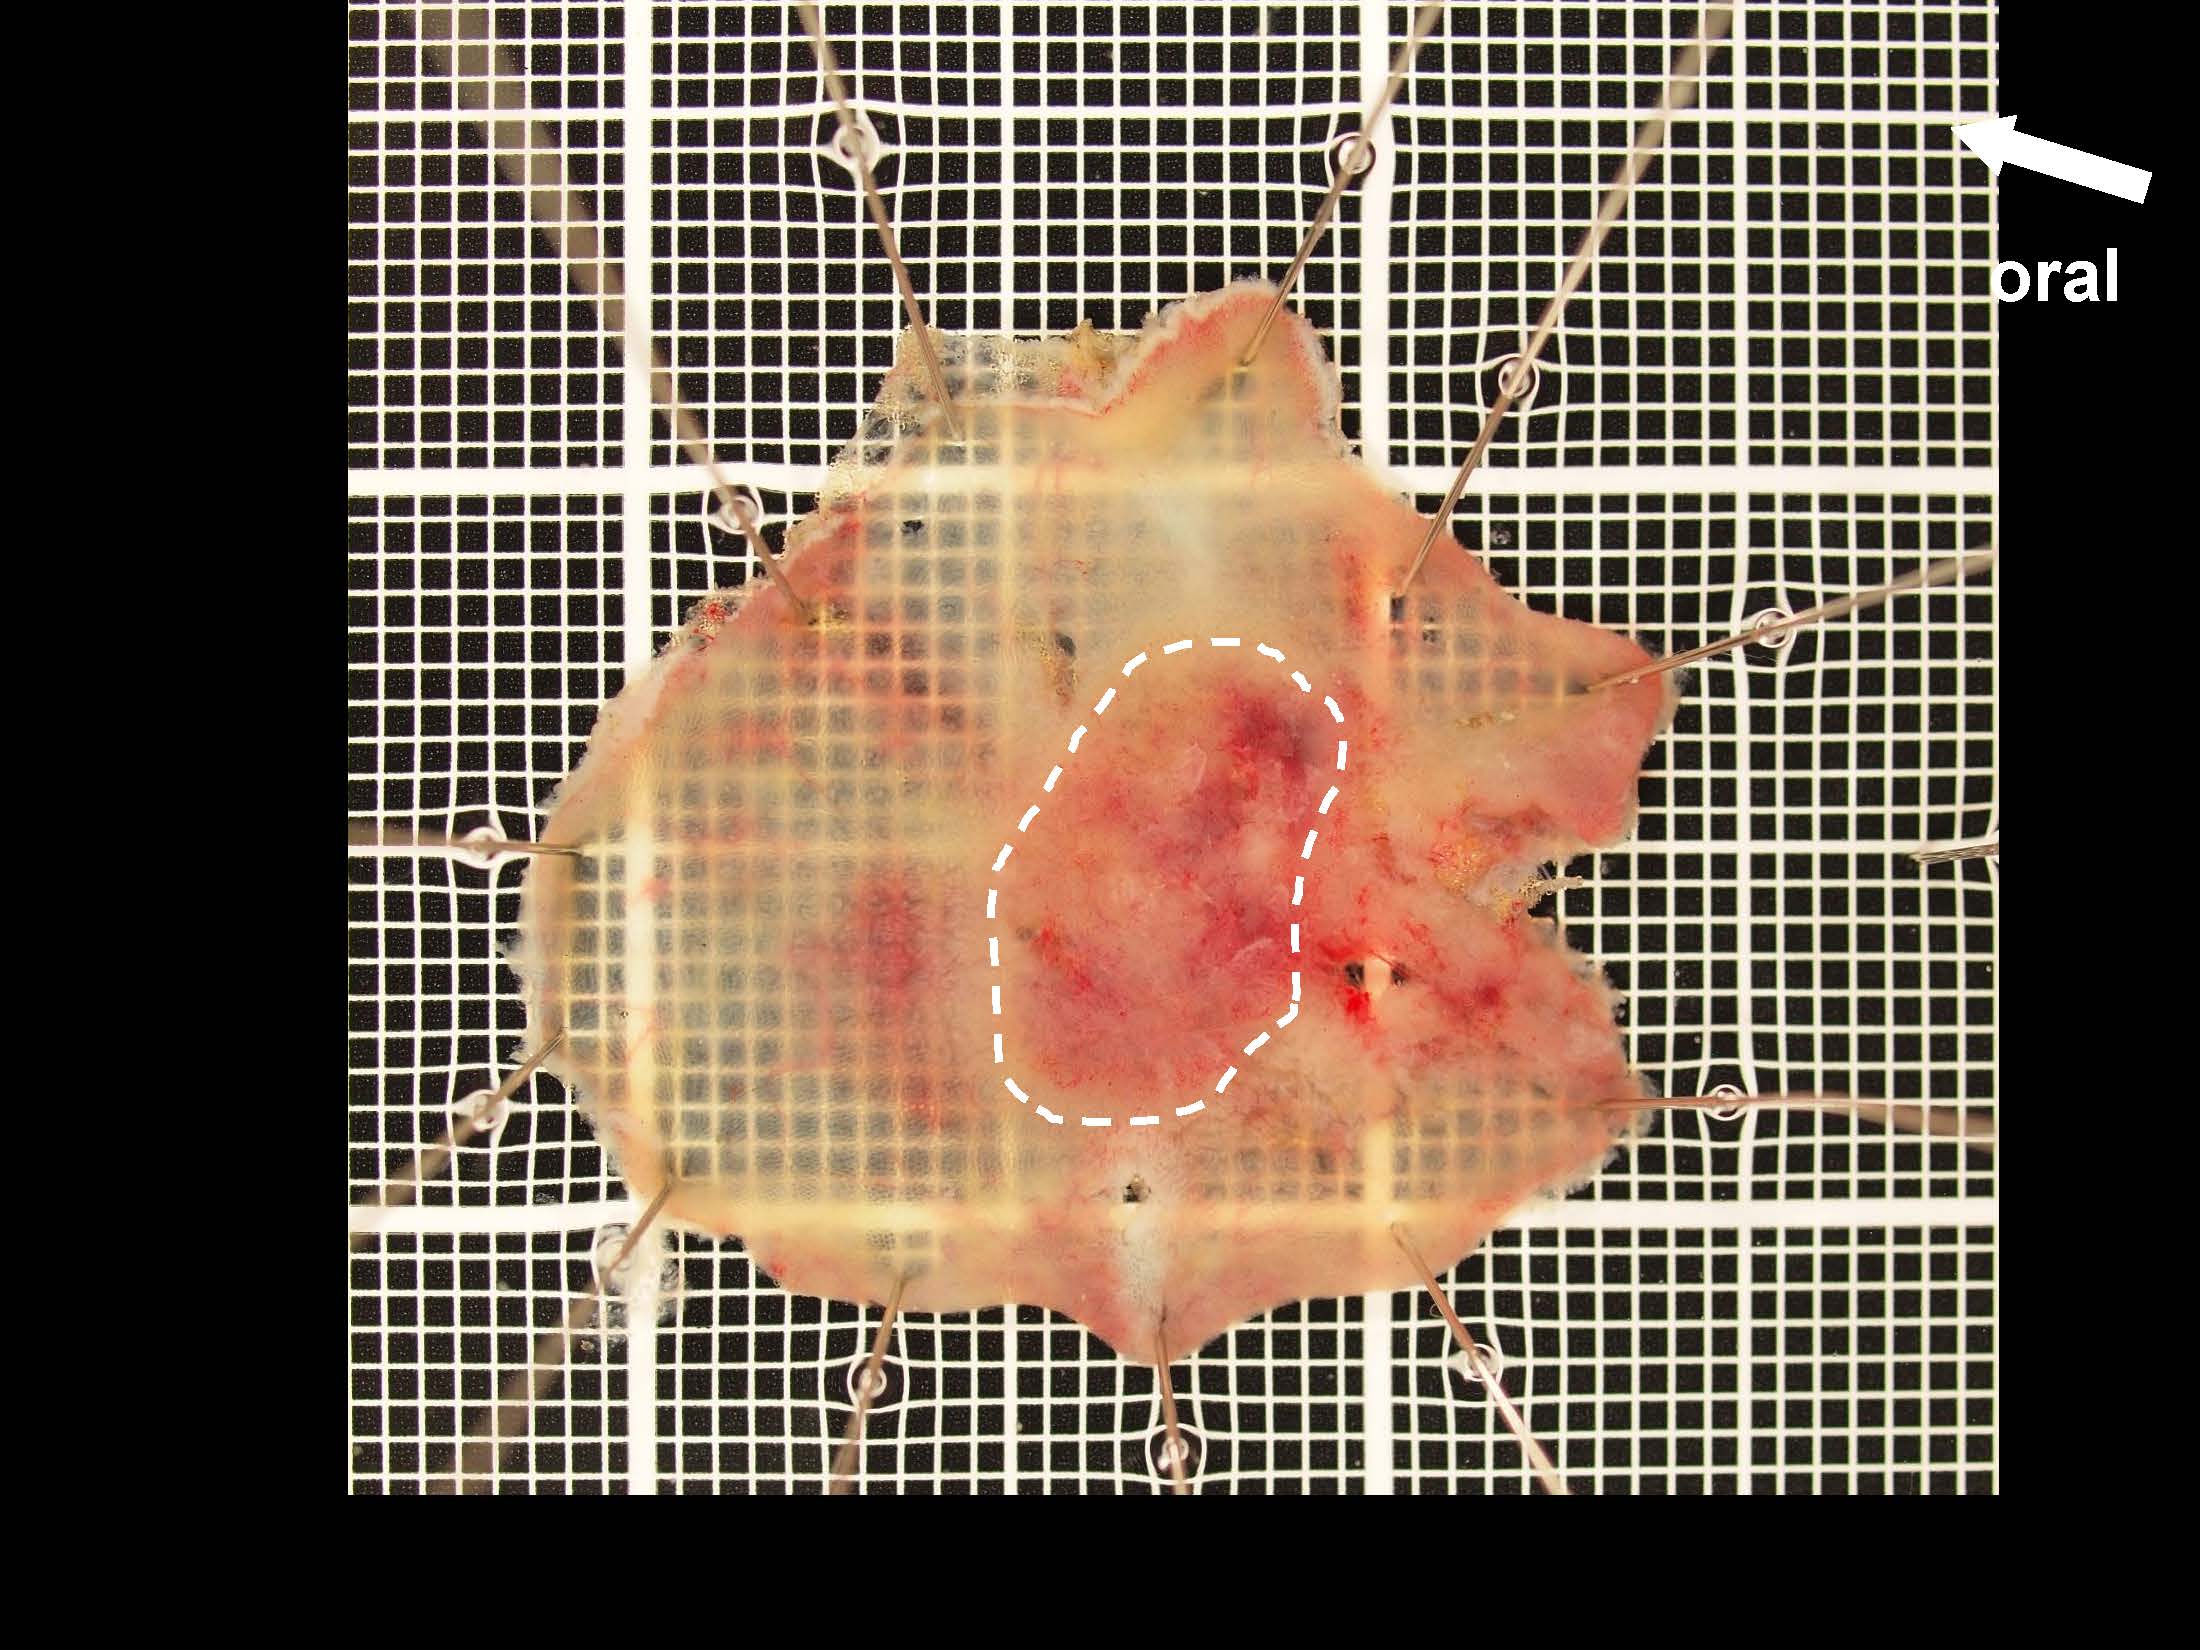

消化管Mapping~大腸~ 2021.10.27

消化管Mapping~大腸~

消化器内科

内視鏡検査・治療

消化管Mapping